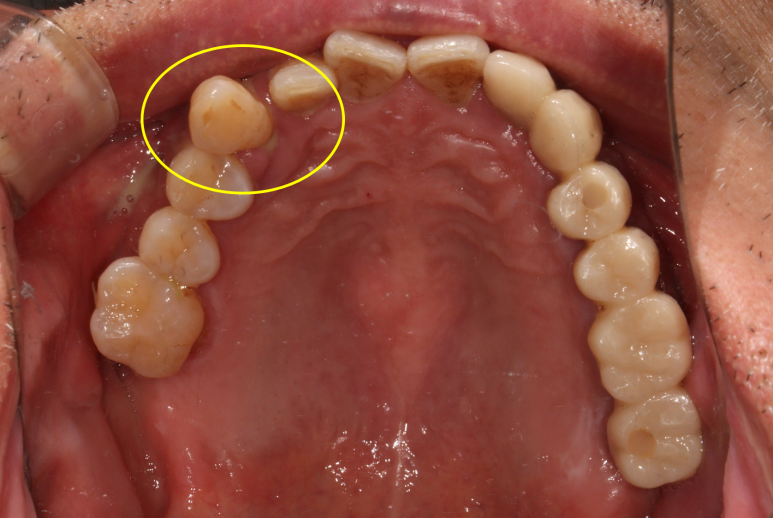

바로 요기가 새로 제작한 지르코니아 앞니 브릿지입니다.

감쪽같은 앞니 치료 아니겠습니까!! 크... 제가 봐도 칭찬합니다.

입천장에서 바라보면 이제 가지런히 정렬되어있는 치아의 배열을 보실 수 있으실겁니다.